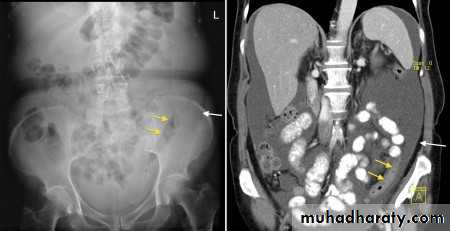

Abdominal calcifications

13. Renal stones and other calcifications of the urinary tract

11. Pancreatic calcification: occur in chronic pancreatitis & diagnosed from it's position

12. Faecoliths seen in colonic diverticulae or in the appendix. The presence of appendicolith is a strong indicator of acute appendicitis, often with perforation.